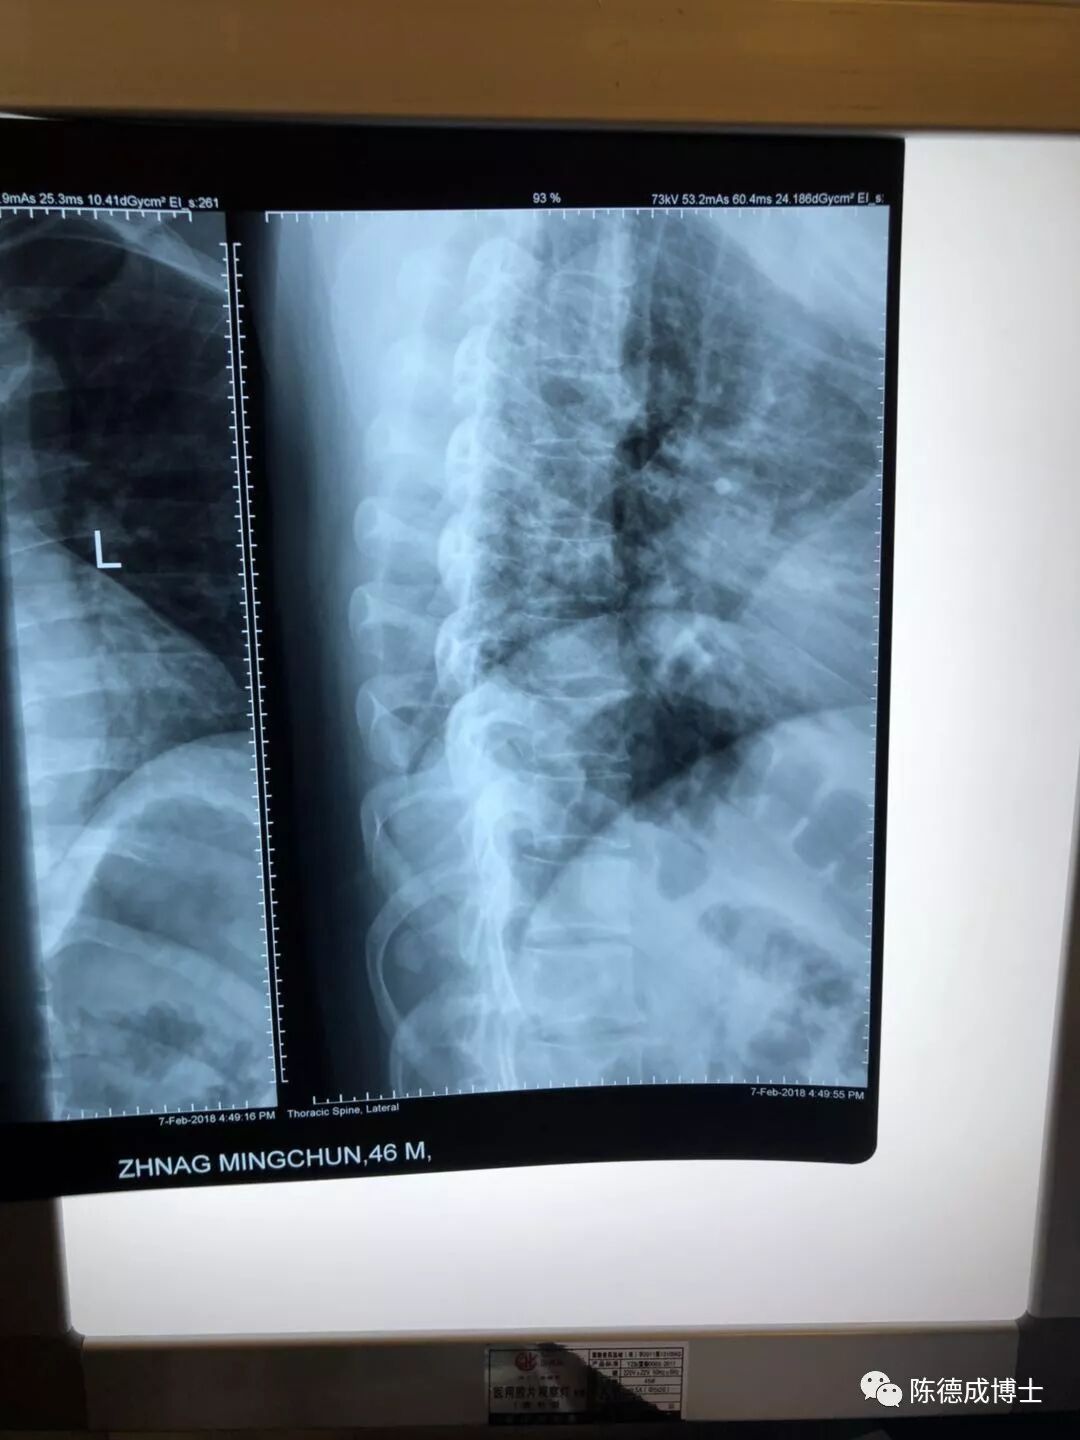

陈博士仔细看了我的胸椎X光片,又进行了触诊。耐心分析了我的病情。把脉、开方、针灸,并教了一套为我量身定制的运动保健操。